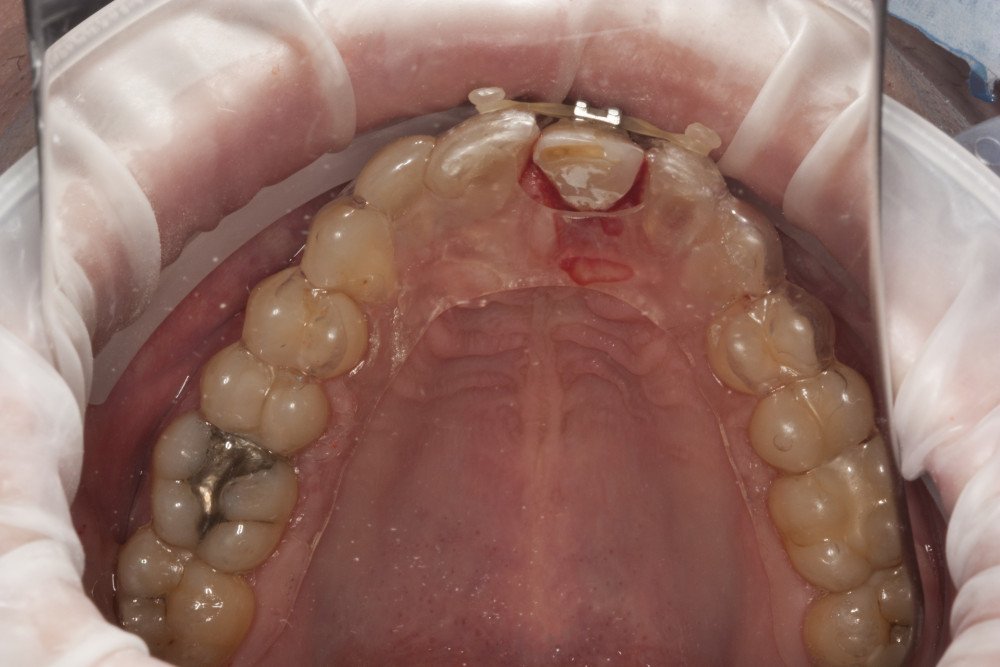

Przykład ekstruzji ortodontycznej za pomocą płytki termoformowalnej i zameczka ortodontycznego: